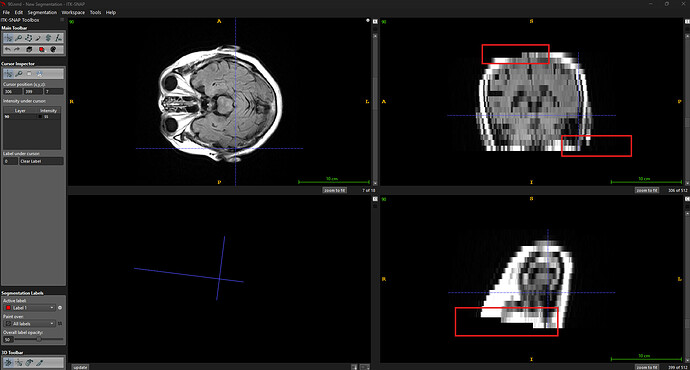

The below code takes the axial volume as input, applies a 90-degree rotation around the z-axis, and writes the output volume to a 90.nrrd file. In 90. When viewing the NRRD file in the ITK-SNAP app, we can see that certain pixels are black in both coronal and sagittal views. You can see this missing area in the attached output image where I have highlighted those regions using red boxes.

Code OUTPUT: